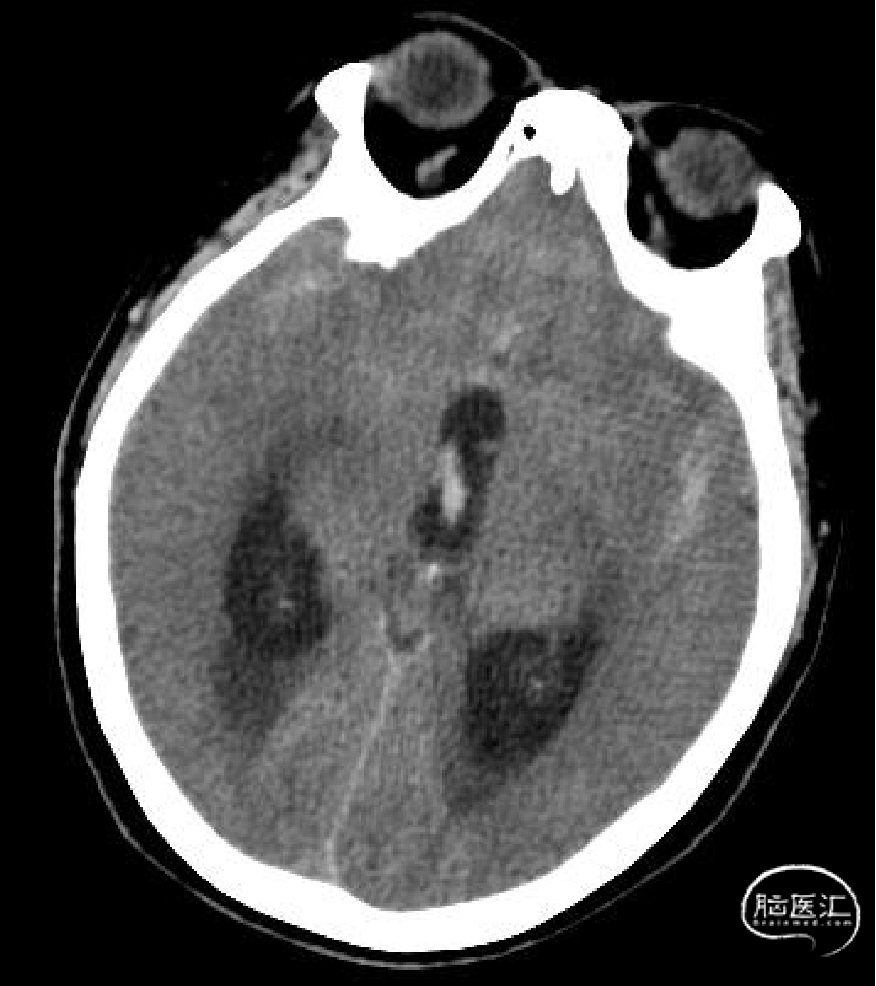

颅脑CT检查显示为SAH,伴急性梗阻性脑积水。